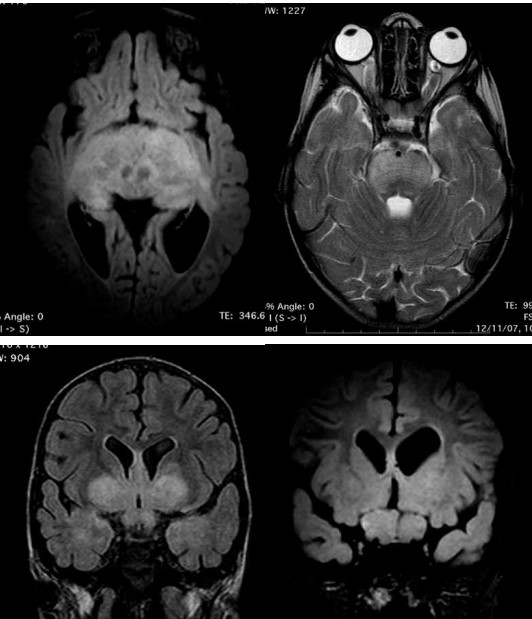

Criança de 03 anos de idade realizou ressonância magnética (RM) de crânio, apresentada a seguir, devido à queixa de cefaleia, associada a alterações visuais e baixa estatura.

(Arquivo pessoal; imagem usada com autorização)

Em relação aos achados das imagens, assinale a alternativa correta.